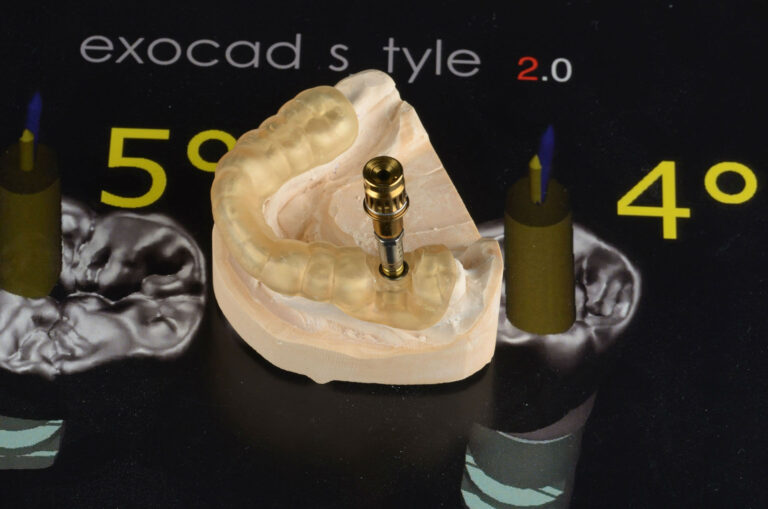

– При тях циментирането на коронката към надстройката /абатмънта/ на импланта се извършва вън от устата и след това абатмънт и коронка – едно цяло, се завиват към импланта, т.е. няма никаква опасност от оставане на фиксиращ цимент около зъбните импланти. Елиминирана е възможността да остане залепващ цимент, който може да предизвика патологични възпалителни процеси, особенно ако зъбните импланти са разположени по-дълбоко в коста. Новите форми на надстройки върху зъбни импланти са т.н. Universal base или Titanium base. Отгоре остава отвор, през който с помощта на винт коронката се прикрепя към зъбния имплант. След като коронката се фиксира към импланта чрез винта, отвора се затваря с композит.

– Завиващите се корони и мостове изискват задължително използване на – сканиране на обекта /вътре в устата или на модел/, виртуално 3D проектиране, изрязване от милинг машина, синтероване и накрая оцветяване. Тези съвременни технологии CAD/CAM позволяват достигането на изключителна точност и прецизност.